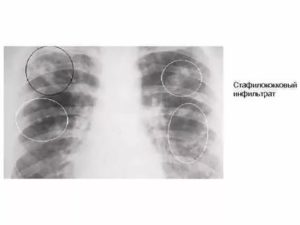

2. Инфильтрат. Заболевание протекает в тяжелой форме. Характерным явлением считается интоксикация. Рентгеновское обследование грудной клетки обнаруживает инфильтративные потемнения, которые часто бывают больших размеров. При лечении они медленно рассасываются.

Рентгеновский снимок поражения легочной ткани при стафилококковой пневмонии